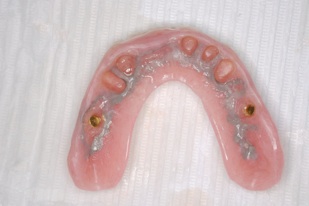

マグネットをつけているので大幅に義歯の面積を縮小することが可能になりました。

術後レントゲンです。このように斜めにインプラントをいれることにより、上顎洞への骨移植をさけることができます。これはオールオンフォーのインプラントを行っている歯科医ならではの発想です。